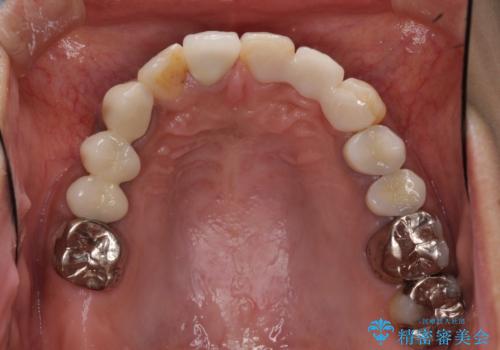

歯を削る量は増えますが、より長い期間再治療なく使用していただくことを最優先に考え、フルカバレッジのオールセラミックブリッジにて補綴することとしました。

他にも、奥歯の銀歯の下にもむし歯が多くあり、痛みが生じていたため、根管治療などを行った上で、オールセラミッククラウンにて補綴治療することとしました。

前歯の裏側の接着面は、隙間ができていたことにより、汚れがたまるだけでなく、むし歯にもなっていました。

我々としては、治療により状態が悪化することだけは避けたいと考えているため、歯全体を覆うクラウンにすることで、より長持ちする治療を提供いたしました。